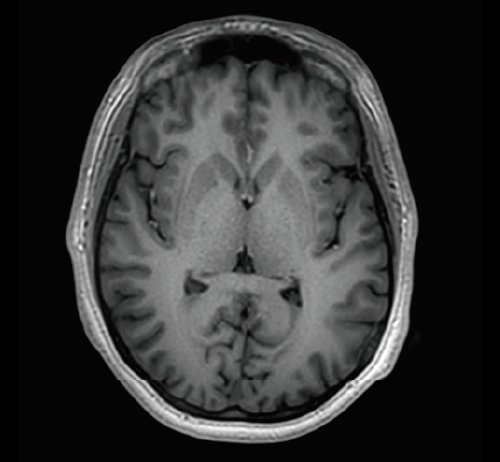

KI-optimiertes Arbeiten und modernste 3T-Technologie machen den Vantage Galan 3T von Canon Medical aus. Canons KI-Anwendung AiCE, kurz für Advanced intelligent Clear-Imagequality Engine, entfernt intelligent das Rauschen und führt zu einer Verbesserung des SNR (Signal-Rausch-Verhältnis). Mit Hilfe der Deep Learning Technologie gelingen besonders klare und deutliche Bilder. Insgesamt ermöglicht die KI-Unterstützung des Vantage Galan 3T somit nicht nur eine höhere Auflösung der Bilder, sondern verkürzt in vielen Fällen auch die Aufnahmezeit.

Mit der PURERF-Technologie und der PUREGradienten-Technologie werden das SNR um bis zu 20% verbessert und Diffusionsbilder optimiert.

• AiCE KI-Technologie zur Entfernung von Bildrauschen und Verbesserung des SNR

• Verbesserung des SNR um bis zu 20% durch PURERF-Technologie